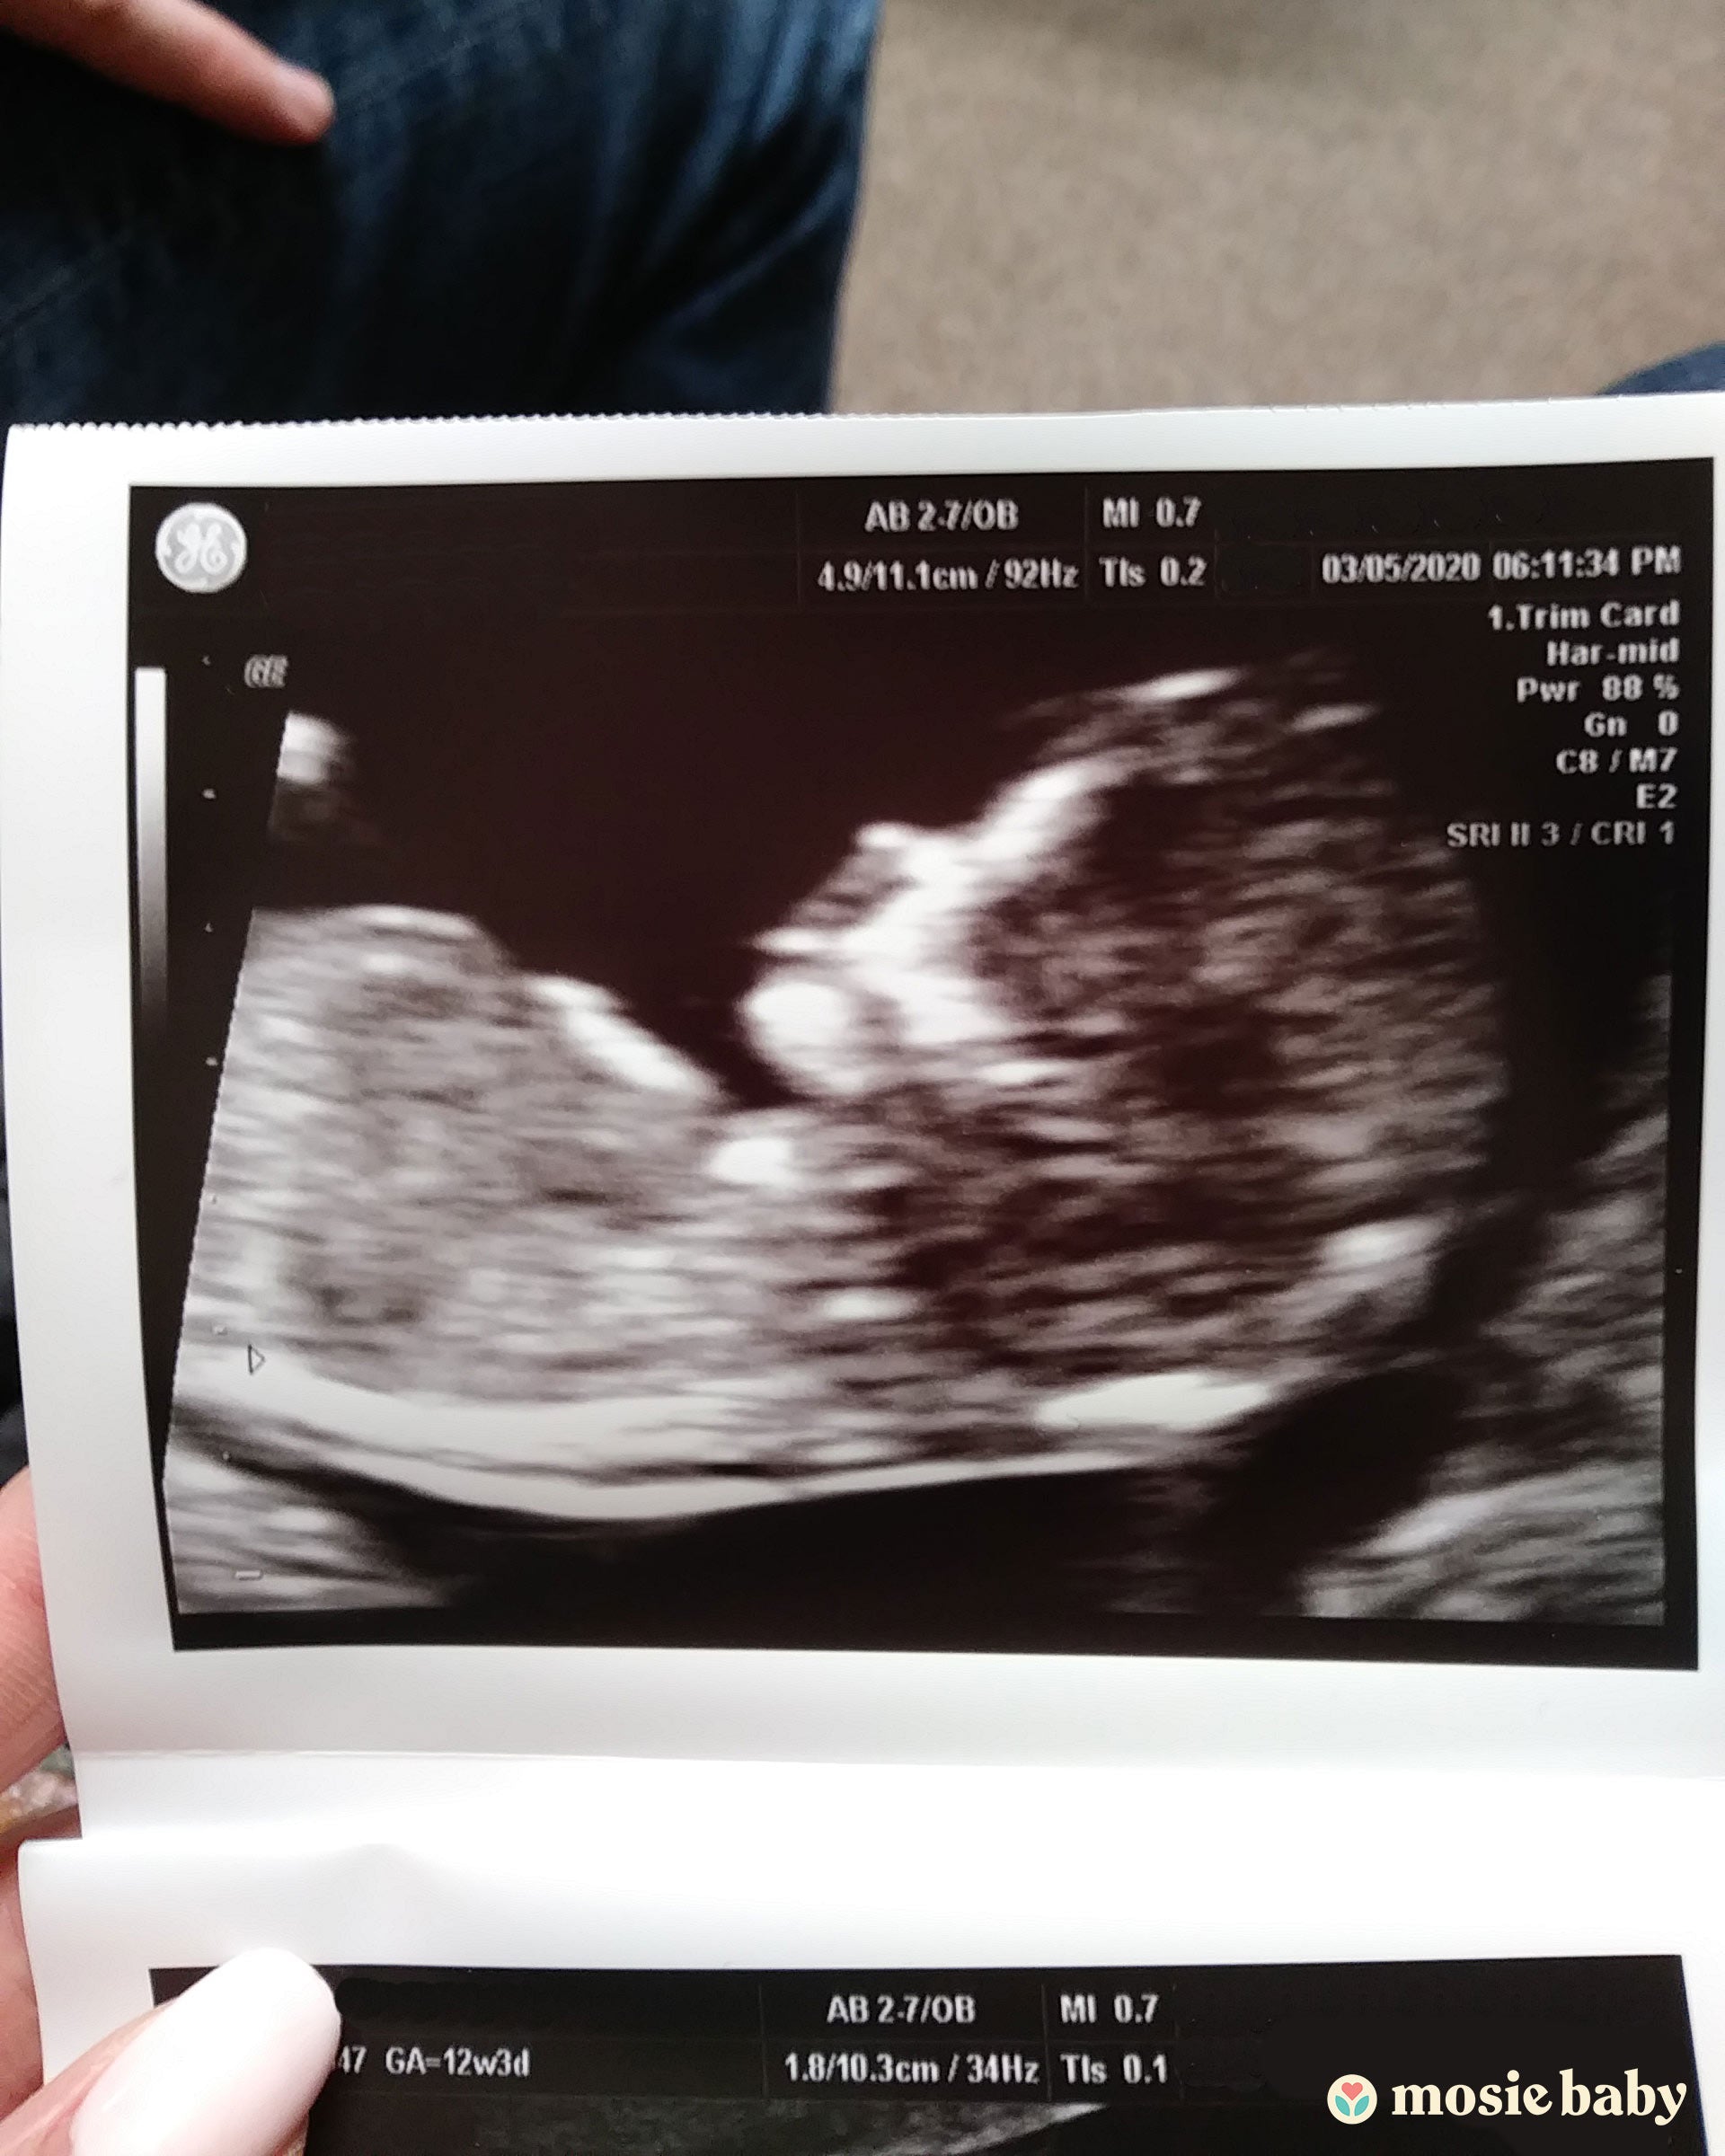

We have been trying for five years to conceive. After two years we went to the doctors and tried two rounds of IUI. My insurance doesn't cover anything under infertility so it was all out of pocket. We were able to get pregnant naturally two years ago, but it ended in a miscarriage at eight weeks. Devastated we started to look into adoption. We have been in the process for over a year. We did try Mosie, and the second month we became pregnant but had a chemical miscarriage. We tried one more time with Mosie and now are 13 weeks, and all is going well so far!